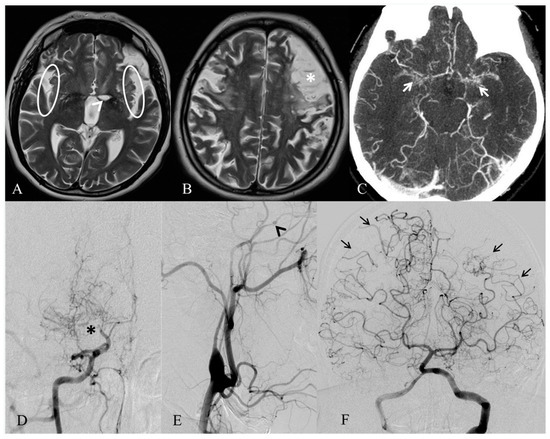

2. Case Report